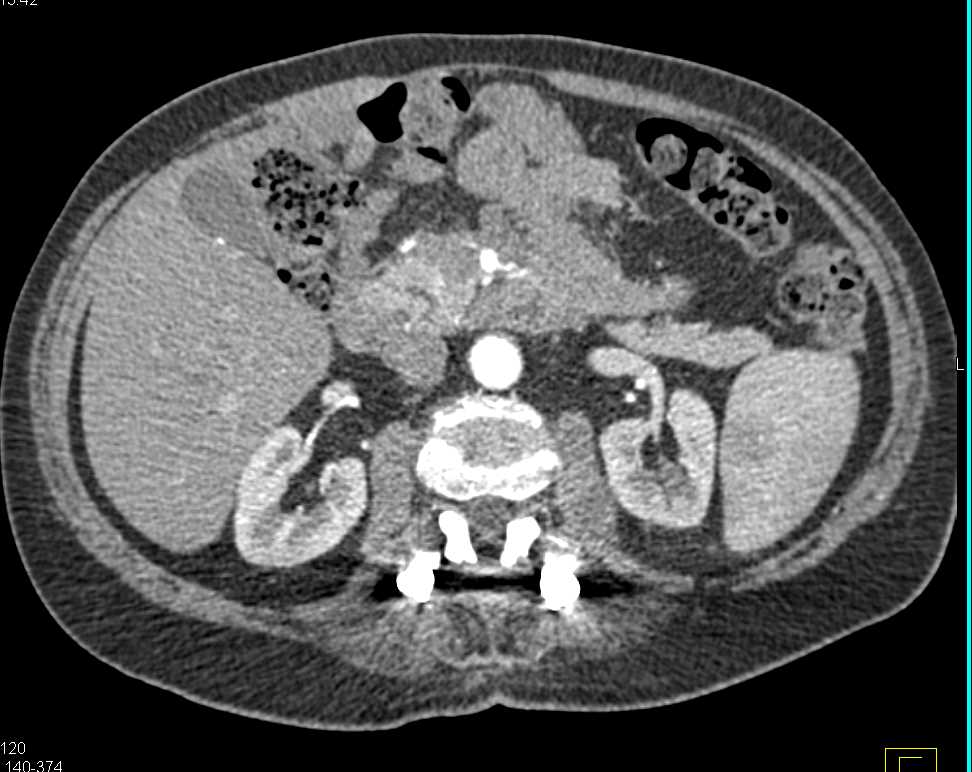

Metastatic Renal Cell Carcinoma to Contralateral Kidney and Pancreas